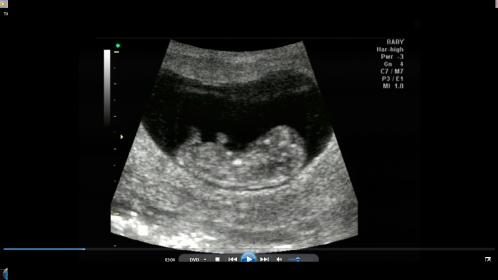

So I went through and grabbed from the video what I saw.

How much hope would you give up of a girl at 10 weeks 4 days?

And yes I know its super early ... and I'm crazy